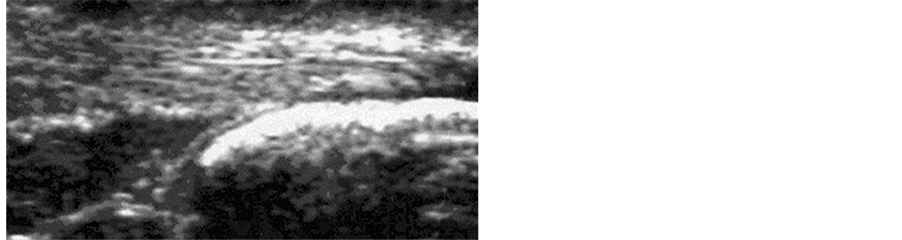

For all subjects of the group A, the echography at T0 demonstrated the presence of an area of hypoechogenicity in the mid portion of the Achilles tendon with an increase of the microvascularity (Figure 1). In group B subjects an absence of alteration in the echographic characteristics of the tendon was demonstrated (Figure 2).

Figure 2. Group B, before treatment: normal tendon and vascularity.